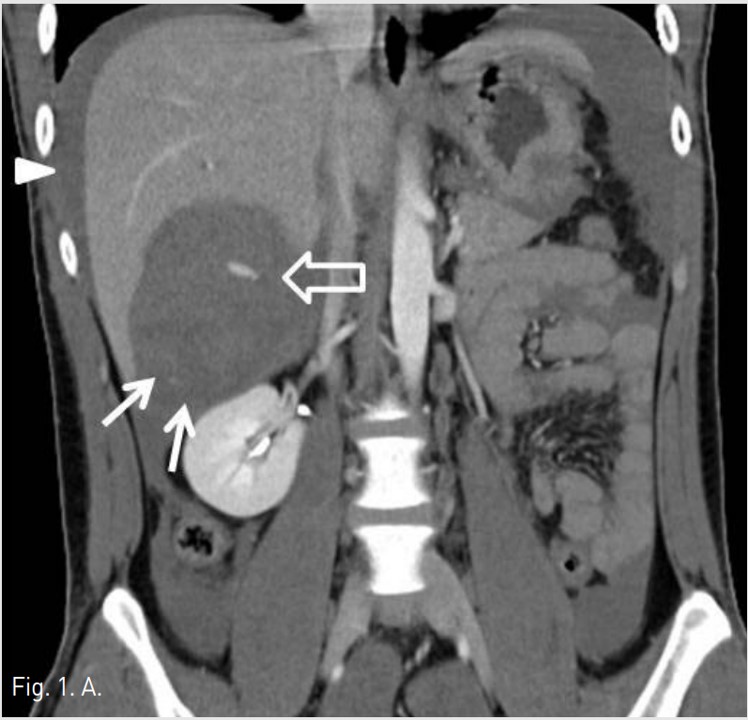

5F RH catheter (Cook, Bloomington, USA)를 이용하여 바로 시행한 간동맥조영술에서 right posterior inferior hepatic branch에서 급성출혈이 관찰되었다(Fig. 1B). 2.9F coaxial microcatheter(Stride, ASAHI, Aichi, Japan) 로 출혈혈관부위를 초선택한 후 gelatin sponge(Cutanplast, Mascia Brunelli , Milan, Italy)을 이용하여 색전술을 시행하였다(Fig. 1C). 시술 다음날 혈색소 수치는 10.0g/dL로 증가하였다. 그러나 시술 2일 후 환자의 활력징후는 혈압 131/80mmHg, 맥박수 82/min로 안정적이었지만, 혈색소가 7.8g/dL로 급격히 감소하였고, 우상복부에 심한 통증을 호소하여 재출혈의 의심하에 복부 CT검사를 시행하였다. CT검사에서 간에 다량의 피막하 혈종이 관찰되었지만, 조영제의 혈관외 유출은 보이지 않았다(AAST grade Ⅲ)(Fig. 2A). 같은 날 시행한 간동맥 혈관조영술에서 기존 색전술을 시행한 동맥에서의 재관류는 없었지만, 새로 생긴 다른 부위의 피막하혈종 내로 광범위한 다발성 미세출혈이 관찰되었다(Fig. 2B). Microcatheter를 이용하여 각 출혈부위 근처의 segmental artery들을 선택한 후 gelatin sponge를 이용하여 광범위한 부위에 색전술을 시행하였고, 더 이상의 출혈은 관찰되지 않았다(Fig. 2C, D). 시술 후 환자의 혈색소는 정상화되었고 우상복부 통증은 점차 감소하였다. 이 후 뚜렷한 합병증 없이 입원 1달 후 퇴원하였다.

Fig. 2. A

Fig. 2A. The coronal CT image obtained 2 days after embolization shows a large diffuse expanding subcapsular hematoma (arrow).